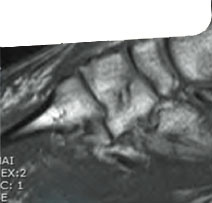

Ressonância Magnética

Músculo Esquelética

Curso Hands On em Ressonância Magnética Músculo Esquelética

Módulo: Membros Inferiores